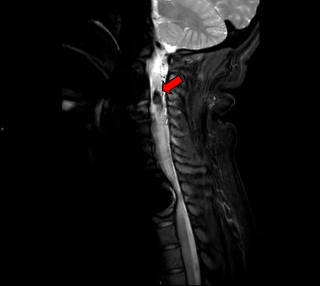

术前MRI提示C3-4髓内占位并破裂出血

患者李女士(化名)是一位38岁的高龄孕妇。孕38周+2天时,她突然出现左侧肢体无力、麻木,症状迅速加重,经过紧急检查,医生发现她颈部脊髓的第3节段有出血,并伴有明显的水肿。最终,她被诊断为颈3-4节段脊髓动静脉畸形并出血。